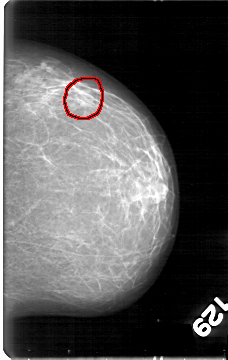

FILE: D_4045_1.LEFT_MLO.OVERLAY

TOTAL_ABNORMALITIES 1

ABNORMALITY 1

LESION_TYPE MASS SHAPE LOBULATED MARGINS OBSCURED

ASSESSMENT 0

SUBTLETY 3

PATHOLOGY BENIGN

TOTAL_OUTLINES 1

BOUNDARY